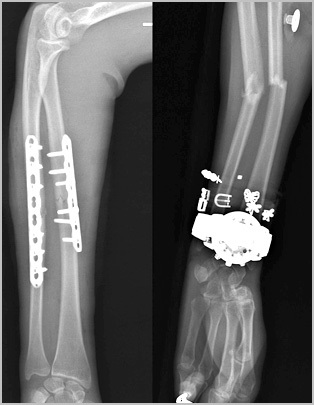

Mai des decât alte fixatori pentru fracturi ale radius și cubitus cu ajutorul plăcii și șuruburi speciale. Osteosinteza raza fracturat și cubitus este „standardul de aur“, în traumatologie.

Plăci moderne și șuruburi permit fixarea fragmentelor de fractură în punctul anatomică corectă de vedere al situației, precum și de mână a avut loc această poziție până când uniunea fractură.

fuziune osoasă diafizare la adult durează o perioadă lungă de timp. După șase săptămâni de pe X-ray puteți vedea primele semne ale calus. După 10 săptămâni, os rezistența fractură în regiunea de până la 80 la sută din original. consolidare completă și restructurare a osului poate dura până la câțiva ani. Odată ce fractura a crescut împreună, ne putem gândi la eliminarea metallofiksatora, deși acest lucru este opțională. În unele cazuri, mettalofiksator poate provoca disconfort, un sentiment de tandrețe. De obicei, tije și plăci ale radius și cubitus oasele sunt eliminate nu mai devreme de 2 ani, cu condiția ca semne radiologice de consolidare fracturii.